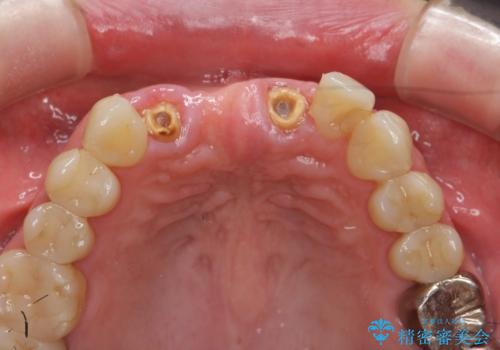

前歯が折れた 前歯部審美セラミックブリッジ治療

- ブリッジの根元が折れ、審美性の改善・治療を求めて来院されました。

保存の難しい歯を抜去しロングブリッジによる補綴を選択しました。